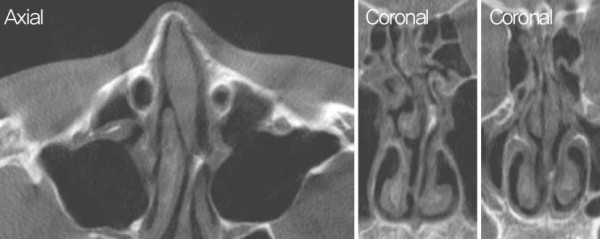

수술 전 CT 사진. 비중격 상단부의 좌측으로 만곡이 관찰되었다.

수술 전 CT 사진. 비중격 미단부가 우측으로 전위된 모습이 관찰되었다. 좌측

cleft palate 및 nasal spine이 우측으로 전위된 모습과 함께 좌측 상악뼈의

일부 소실이 확인되며, 비중격 미단부 변형 및 비익의 변형으로 인한 우측

비밸브 협착이 관찰되었다.

Cottle test로 우측의 positive가 관찰되었으며, 흡기 시 좌측 비익연골의 허탈이 보였다. 또한 CT 검사에서 좌측 cleft palate가 확인되었으며, 좌측 maxilla 일 부의 결손이 관찰되었고, nasal spine이 우측으로 전 위된 모습이 보였다. 비중격은 상단에서 골부에 걸쳐 좌측으로 high septal deviation이 있었으며, 우측 caudal septum이 우측으로 전위된 것이 확인되었다. 또한 비익연골의 내전과 비중격 미단부 변형으로 인한 우측 비밸브 협착이 관찰되었다.